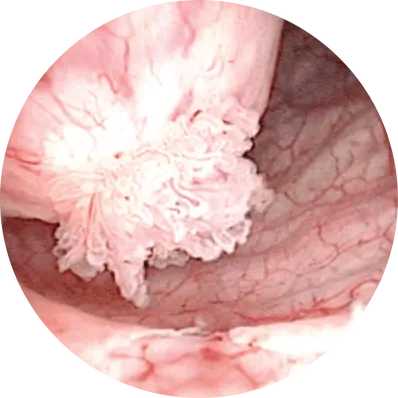

Cystectomy is a major surgical procedure to remove part (partial cystectomy) or the entire bladder (radical cystectomy). It is most often performed for muscle-invasive bladder cancer or high-risk recurrent bladder tumors. In men, it may include removal of the prostate and seminal vesicles; in women, the uterus, ovaries, and part of the vagina may also be removed. A new way for urine storage and drainage (urinary diversion) is created after surgery.

Causes (Leading to Need for Cystectomy)

Diagnosis (Before Surgery)